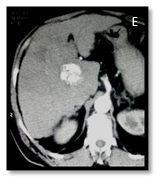

Figure 3A-3C Triphasic CT images for a right hepatic lobe segment V lesion before doing IOUS.

Figure 3D-3F Triphasic CT for the same patient after doing IOUS with enlarged sized of the right lobe lesion and newly developed caudate lesion that treated by combined RFA and TACE.